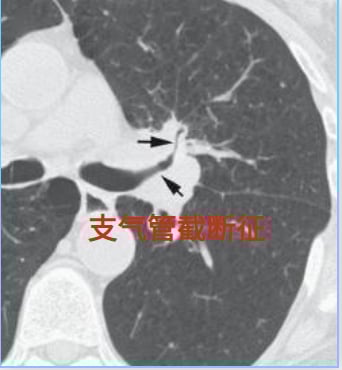

六、支气管截断征:气道被肿瘤阻断

支气管截断征是指支气管壁因癌肿的侵蚀、破坏和占位,导致支气管突然中断,呈杯口状平直或漏斗状截断。在X线片上,阻塞远端肺纹理的突然缺失清晰可见。这是肺癌极具辨识度的CT征象之一。然而,需要警惕的是,创伤性气管损伤、支气管闭锁、肺隔离症、支气管囊肿、支气管异物等良性病变也可能呈现类似征象,因此需要结合临床情况进行仔细鉴别诊断。